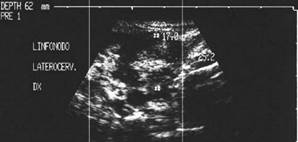

Barbat de 45 ani.

Recidiva linfonodala laterocervicala dreapta dupa tiroidectomie in urma cu trei

ani pentru carcinom papilar.